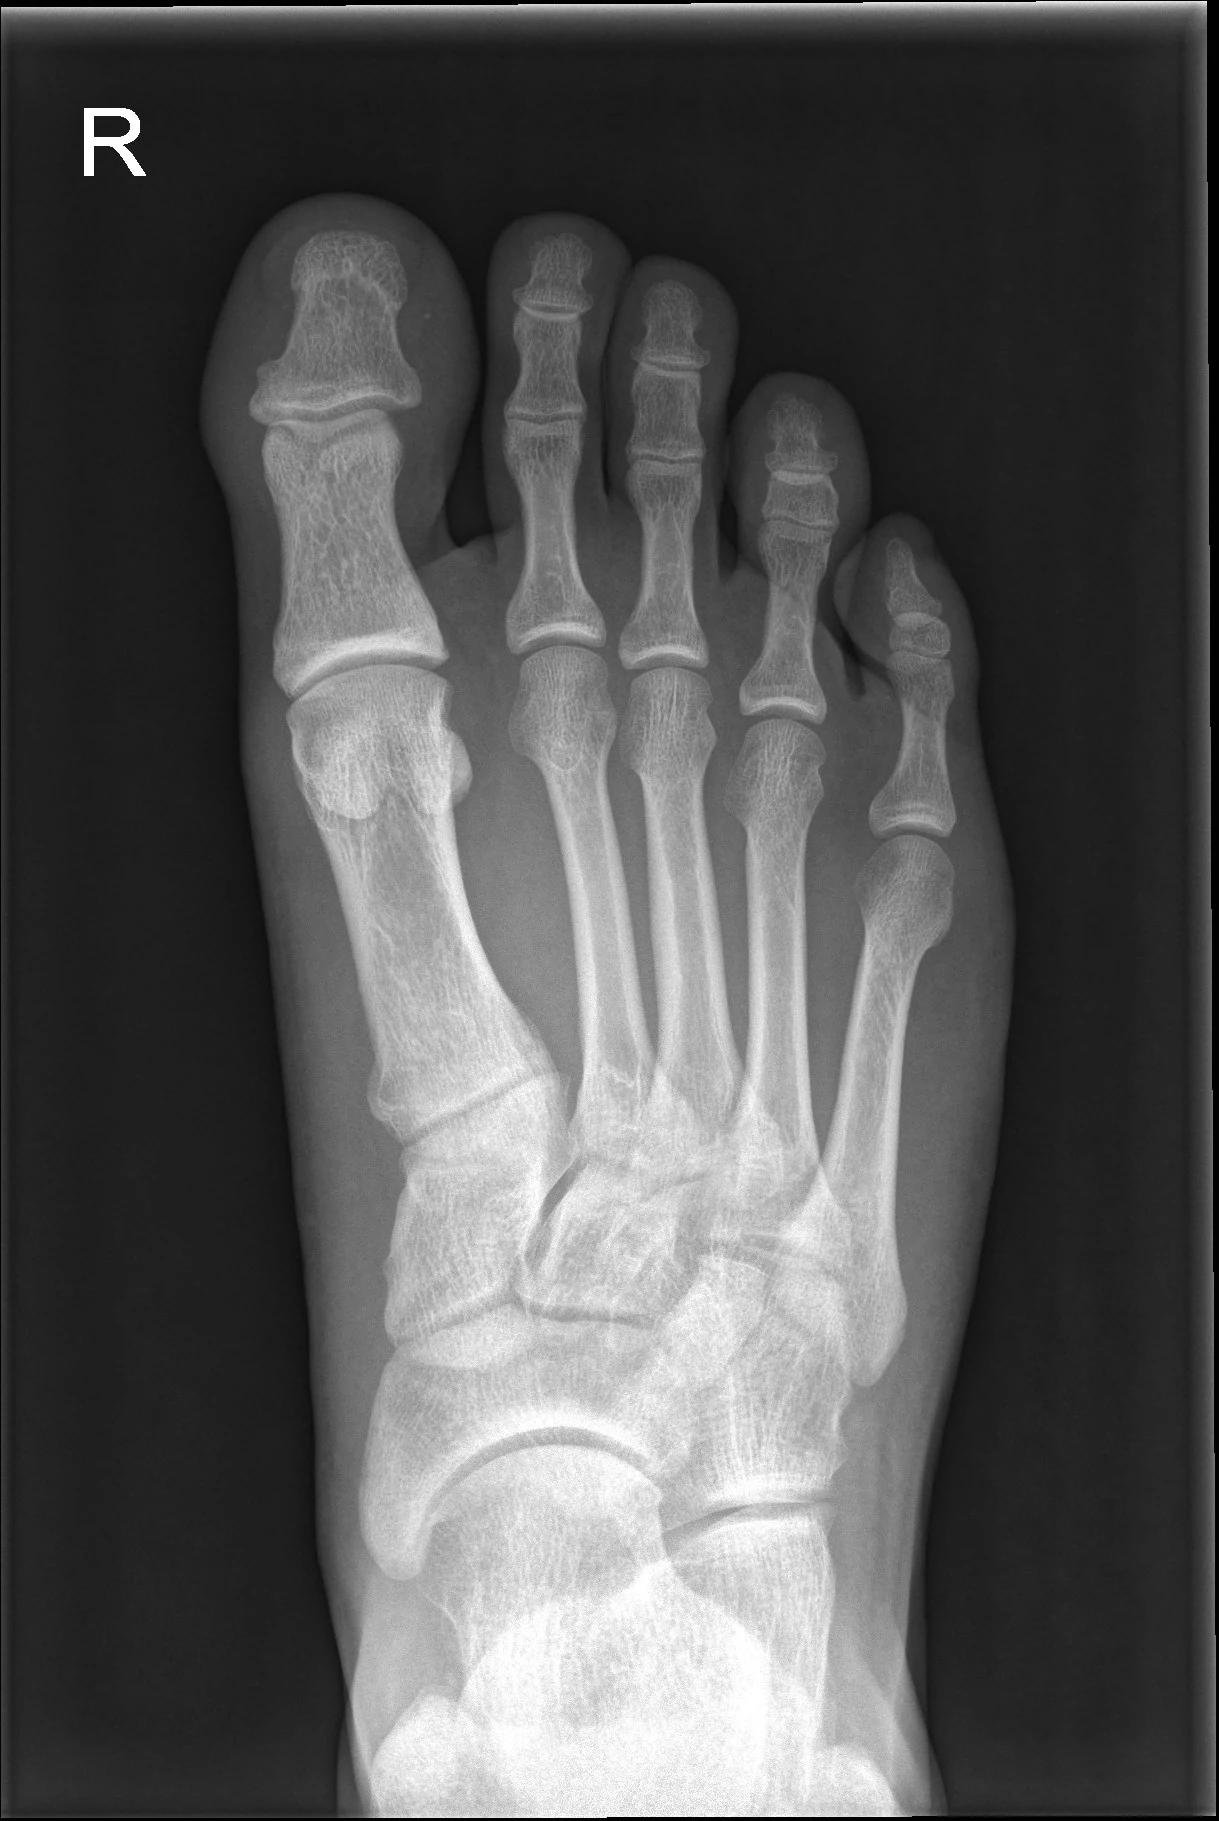

Молодой пациент с травмой спинного мозга страдал от выраженной деформации стопы. Деформация была настолько сильной, что нагрузка перестала распределяться правильно, и возник риск пролежней и угрозы ампутации.

Целью операции было вернуть скелет стопы в максимально нормальное положение. Сложность заключалась в том, чтобы учесть существовавший ранее неврологический дефицит. Стопа была исправлена хирургическим путем и стабилизирована внешним фиксатором для обеспечения долгосрочного выравнивания.

Благодаря успешной операции ногу удалось сохранить. Новое положение стопы позволяет значительно лучше распределять нагрузку и значительно улучшает подвижность пациента.